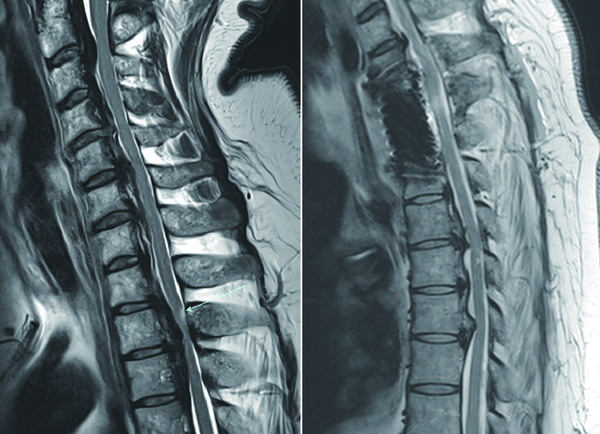

후종인대골화증은 척추 뒤쪽에서 탄성을 유지해 주는 후종인대가 유전적 요인으로 서서히 석회화되면서 척수를 압박해 팔·다리 기능이 점점 저하되는 질환이다. 이로 인해 활동력이 떨어져 비만·당뇨 같은 합병증이 동반되기 쉽다. 초기에는 통증이 없어 진단이 늦어지는 경우가 많고, 진행되면 균형 감각과 근력이 떨어져 보행이 힘들어지고 잘 넘어진다. 더 악화되면 가벼운 넘어짐으로도 사지마비나 호흡마비로 이어져 생명을 위협할 수 있다.

A씨의 경우 흉추 2·3번 부위에 후종인대골화증이 발생해 수술 부위가 깊고 석회화가 심해 수술 난이도가 매우 높을 것으로 예상됐다. 임 교수는 그간 40여 건의 흉골병경유 전방접근술(Tranmanubrial approach) 경험을 바탕으로, 심장에서 나오는 대혈관을 더 효과적으로 견인할 수 있는 장치까지 새로 마련하며 철저히 준비했다. 수술은 석회화된 후종인대와 손상된 척추체를 안전하게 제거한 뒤, 임 교수가 직접 고안한 척추용 케이지를 삽입해 절제 부위를 재건·보강했다. 환자는 수술 다음 날부터 하지 기능이 빠르게 회복돼 보조기 없이 보행할 수 있을 정도로 호전됐다.